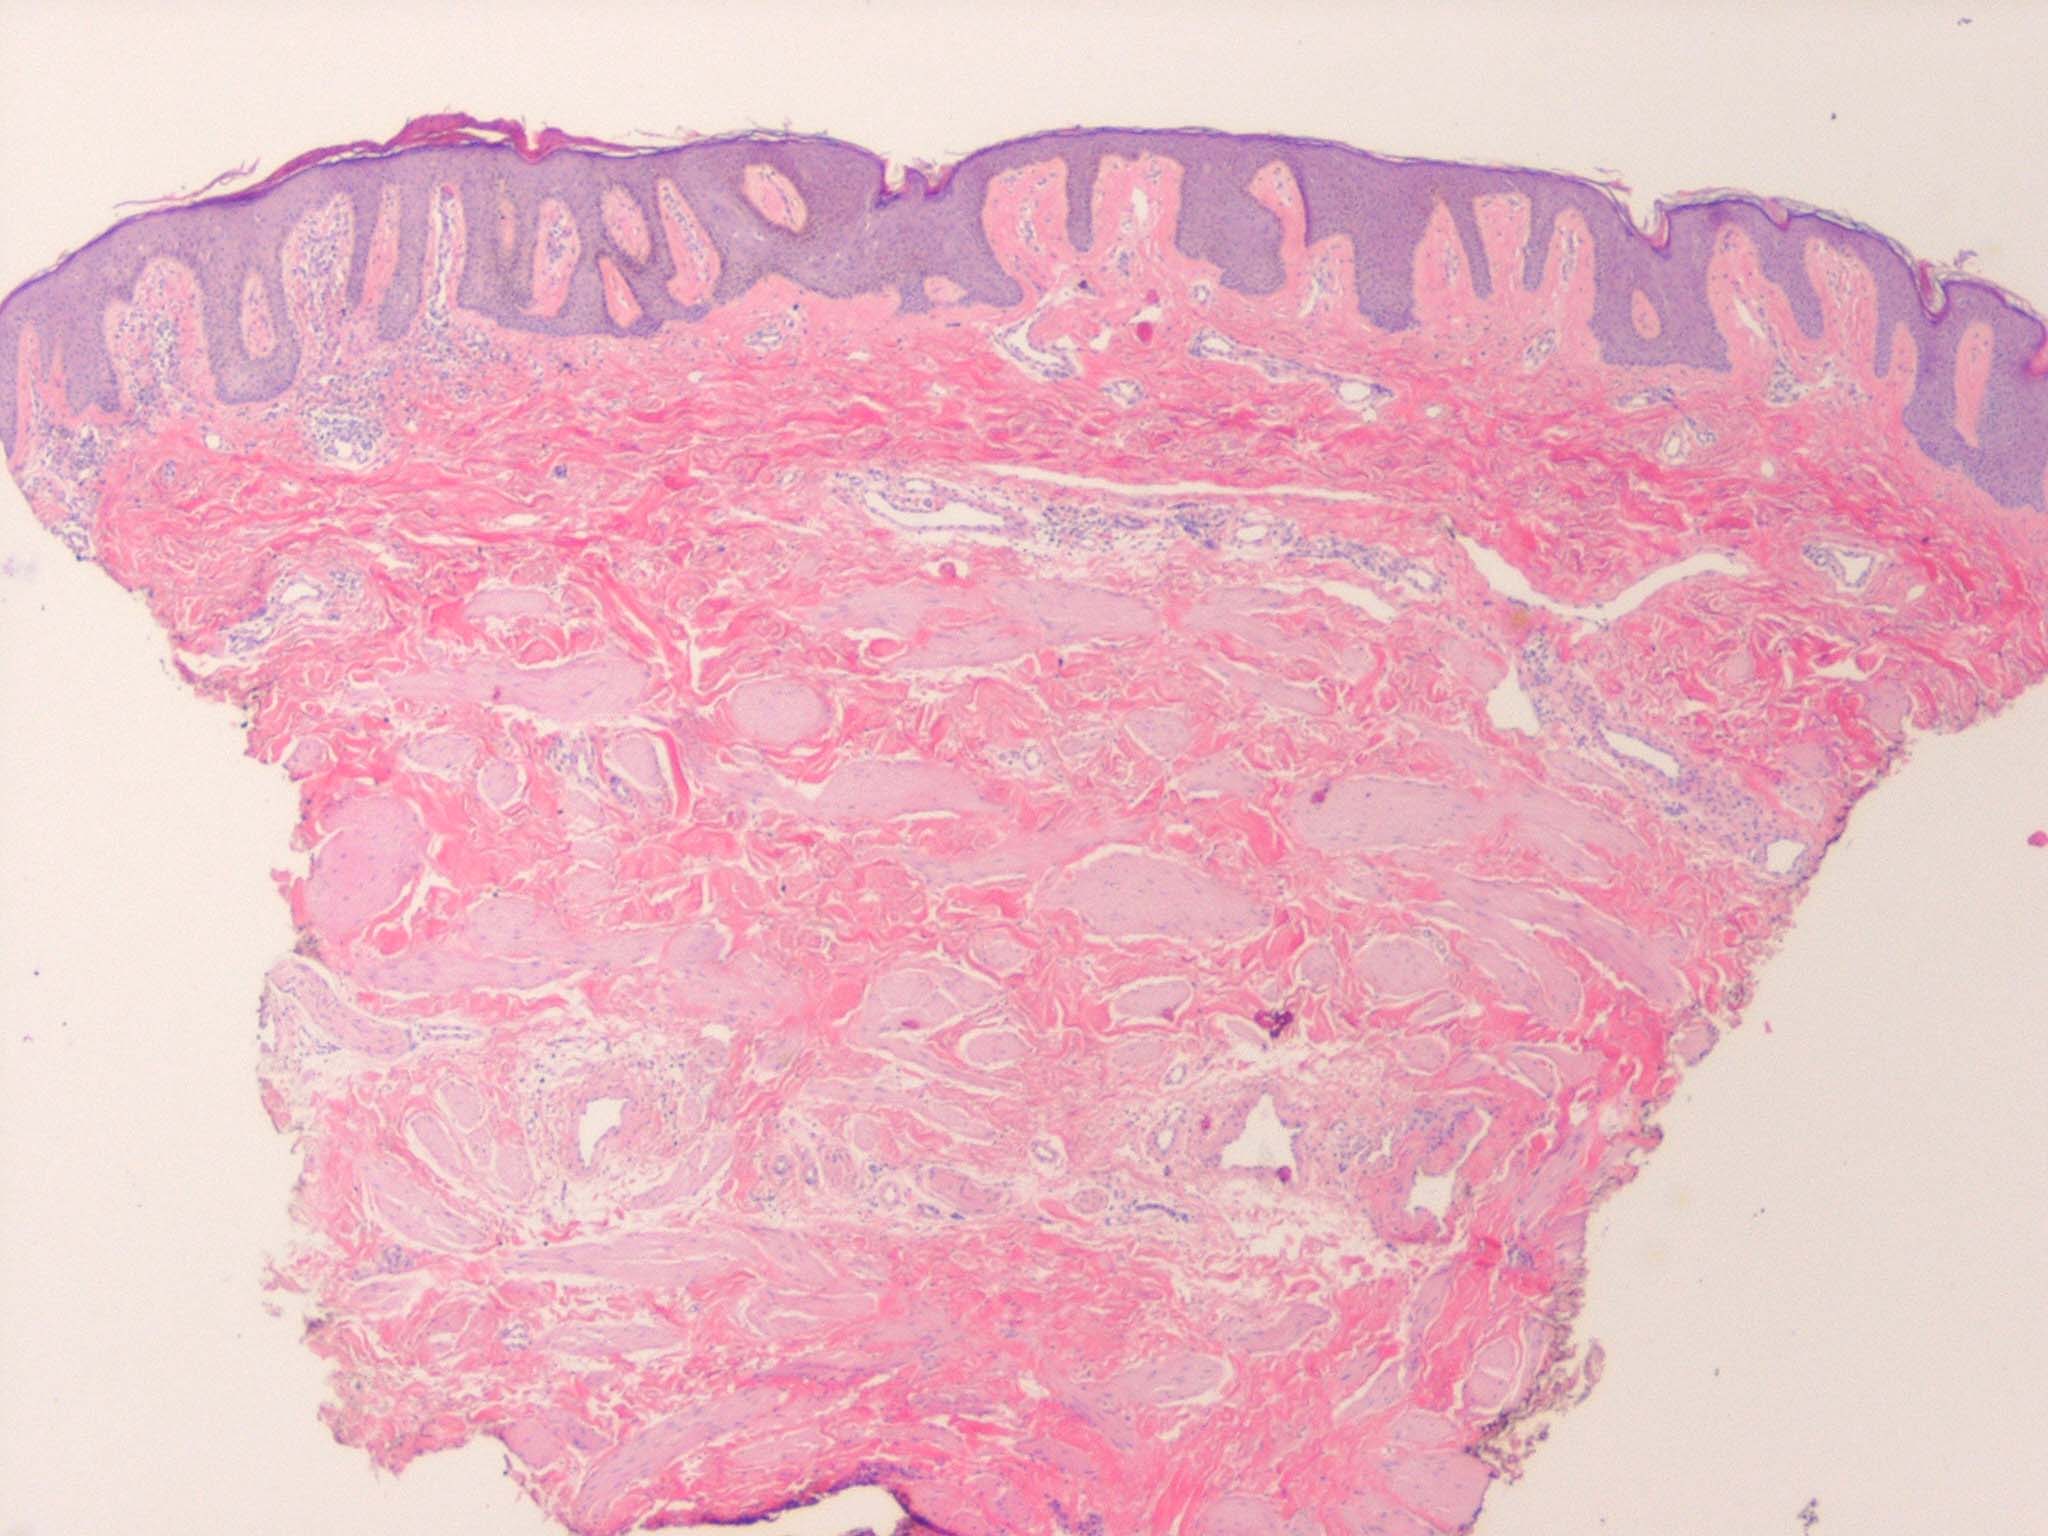

Accessory Nipple

The histologic features of a supernumerary nipple are identical to that of the regular nipple, including hyperpigmentation, slight hyperkeratosis with epidermal thickening, pilosebaceous structure of Montgomery areolar tubercles, smooth muscle bundles typical of the areola, and possible mammary glands and intradermal straight ducts.37 A significant increase in the number of clear cells of Toker has been found in supernumerary nipple tissue, indicating supernumerary nipple may be a precursor of extramammary Paget disease